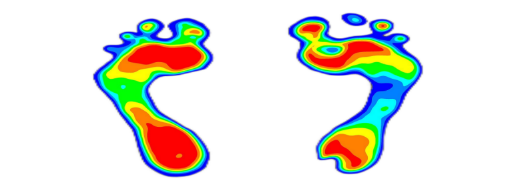

足底压力检测法:足底压力的分布情况和力量情况,足部的形态和功能、静态站立足底压力评估、动态走路足底压力评估